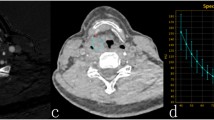

Each patient’s head and neck MRI examinations before and after induction chemotherapy were retrieved from the hospital’s PACS system, and the DICOM format images of all sequences were exported. The ITK-SNAP software (Fig. www.itksnap.org, Version3.8.0) imports the images and selects the transaxial T1WI sequence to store it as the original image. Since parotid segmentation needs to be repeated at different time points and manual segmentation is time-consuming, we developed a deep learning model for semi-automated segmentation of the parotid regions for efficient segmentation. The parotid gland was manually segmented layer-by-layer on the T1WI sequence before treatment, then stored as regions of interest (ROIs). A deep learning model was established on the U2 Netp network using the segmentation results before treatment as a reference (see the Supplementary Materials for specific methods) to segment the images after IC, followed by a further manual correction to obtain semi-automatic segmentation results. The final segmentation results were also verified by a senior head and neck radiologist.